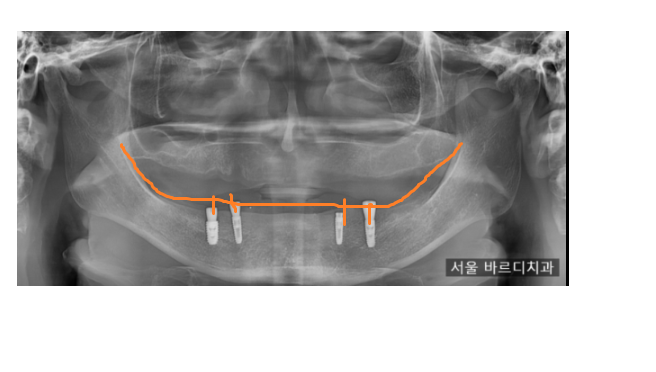

x-ray로 확인해 보면 임플란트가 잘 심어진 것을

확인하실 수 있습니다.

임플란트가 치아 역할을 해주기 때문에

기존 틀니에 비해 씹는 힘이 강하고

잘 안 빠지는 장점이 있습니다.

임플란트를 전체하는 것에 비해

비용도 저렴하고요.

위 환자분은 4개의 임플란트만 심으셨지만

구강 상태에 따라 식립 개수는 달라질 수 있습니다.